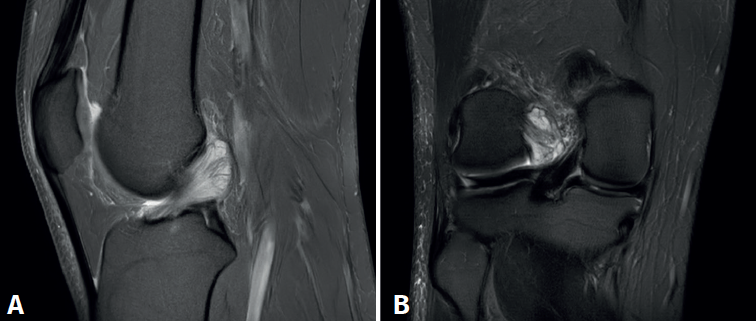

En las pruebas complementarias no presentaba alteraciones óseas en las radiografías en carga anteroposterior y lateral de rodilla. El estudio mediante RM evidenció un ganglión sinovial intercondilar de 25 mm (Figura 2).

Figura 2. Imagen de resonancia magnética del quiste sinovial localizado en el ligamento cruzado anterior en cortes sagitales. A: secuencia DP FS en corte sagital de la rodilla; B: secuencia DP T1 en corte sagital de la rodilla.